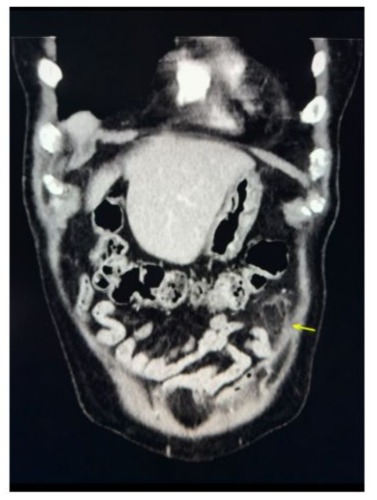

In the emergency department, a CT scan of the abdomen and pelvis revealed mild colonic diverticulosis without signs of acute diverticulitis and left mid-abdomen antimesenteric focal fat infiltration in the epiploic appendages. The figures below are CT scans of the transverse and coronal abdominal views, respectively, illustrating antimesenteric focal fat infiltration in the left mid-abdomen, which suggests EA (Figures 1 and 2). The scan also revealed right lower lobe pulmonary nodules measuring up to 0.6 cm, with a recommendation for chest CT follow-up in 6–12 months. Prominent vascular calcifications were evident in the aortoiliac arteries. A transthoracic echocardiogram (TTE) performed subsequently demonstrated a trileaflet aortic valve with reduced systolic excursion, moderate calcific aortic stenosis, and trace aortic regurgitation. The patient left the ED prior to receiving a formal diagnosis and was later informed of the findings by his internist.

Figure 1: Coronal view of EA with arrow pointing to left mid-abdomen antimesenteric focal fat infiltration.